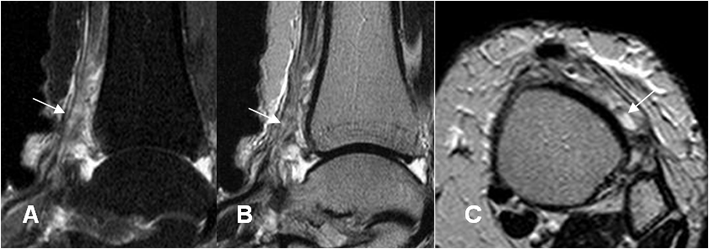

Fig 76. Ruptura tendinosa parcial.

A: RM axial en T2, B: RM sagital en T2 y C: RM sagital en STIR. Tendón engrosado, con zona hiperintensa por tendinitis o ruptura parcial.